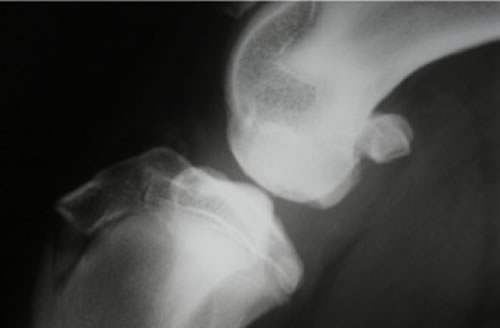

OCD(離断性骨軟骨症)とは

大腿骨骨頭の関節軟骨が成長障害により厚みを増し、損傷を受けやすくなり、軟骨が浮きあがりはがれることで痛みを生じます。

好発犬種

バーニーズ、ゴールデン、ラブラドール、シェパードなど大型犬

レントゲン検査、関節鏡検査

治療

OATS(自家骨軟骨移植)など。軟骨の欠損部に別の部位から採取した本人の正常な軟骨を移植し、関節面での接触を良くし、痛みを取り除きます。大型犬の成長期の跛行は消炎鎮痛剤等による対症療法ですませず、跛行原因の早期診断、早期治療が重要です。